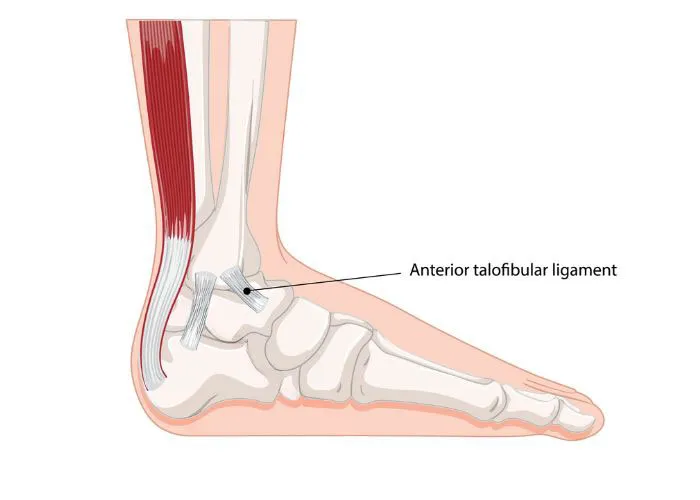

- Ankle: ATFL (most common); Inversion + Plantarflexion. 📌 ATFL: "Always Tears First".

⭐ ATFL: most common ligament in ankle sprains.